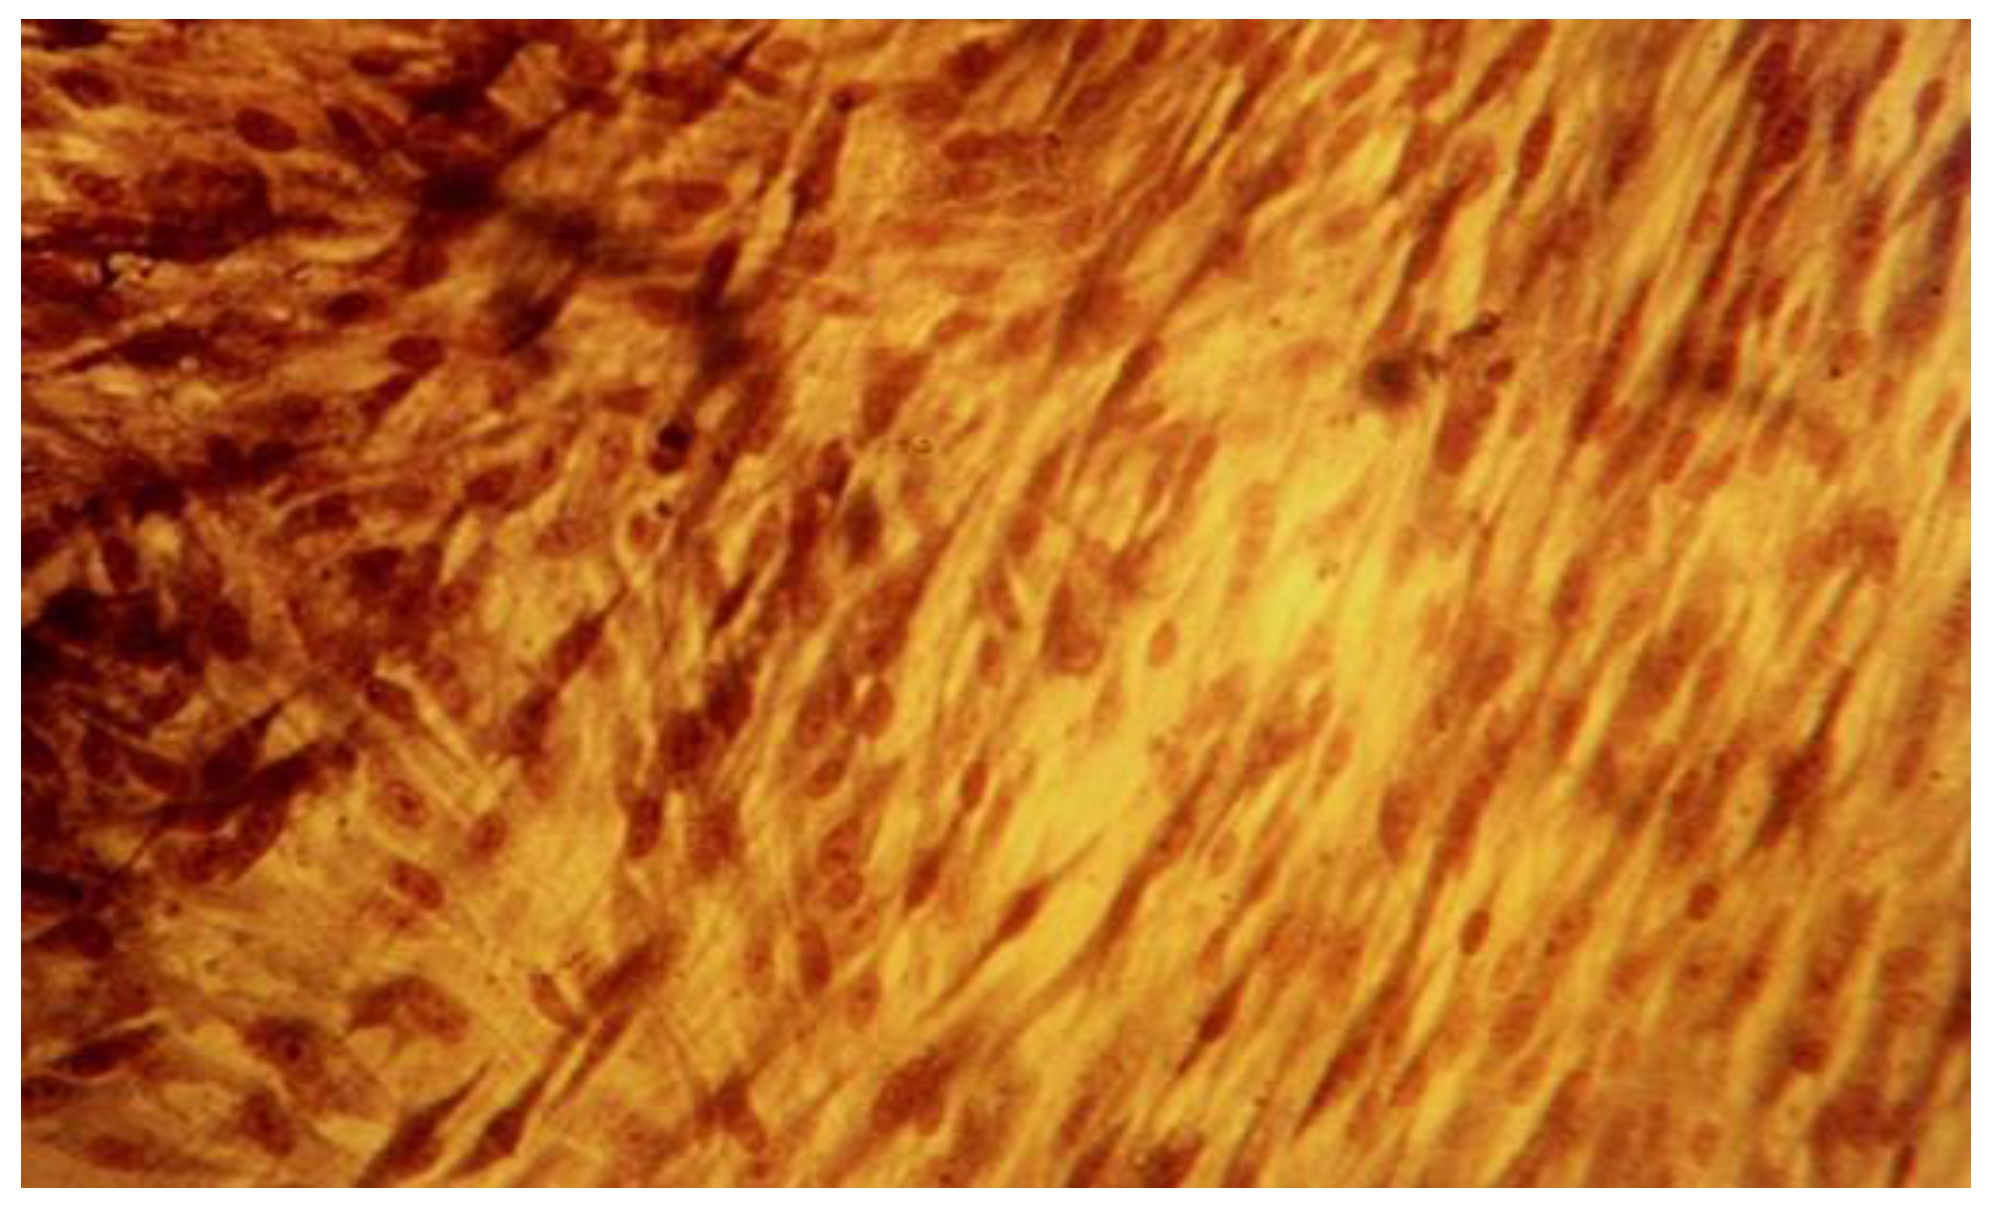

Figure 5.

Fibroblasts cell line L929 at 24-hour mark, MTA Repair HP (Angelus, Brazil) lot, 20x magnification. Degenerative cytoplasmic and membrane alterations.

Figure 6.

Fibroblasts cell line L929 at 96-hour mark, MTA Repair HP (Angelus, Brazil) lot, 40x magnification. Detached cells from monolayer, in suspension.

The qualitative assessment of biological effect by microscopic examination of cellular appearance is consistent with values for the cellular dead rates and cellular density. Different changes in general cellular morphology, whose progressive evolution during the experiment, conducted to death cell, and detachment from substrate, have been observed. The observations indicate more obvious and visible aspects for MTA HP than BD and they have been presented descriptively. Nevertheless, the microscopic evaluations are in general more difficult to be precisely identified and must be always referred to the entire experiment and numerical data obtained. For MTA HP, more visible cell membrane integrity damages were observed, in association with a higher number of floating death cells. Loss of membrane integrity is a clear indicator for an unfavorable prognosis for cell survival [26]. For BD the morphological degenerative cell alterations were more discrete, and the presence of round detached cells less important. The rounded aspect is related to first sign of cellular injury, swelling, later followed by different nuclei and nucleoli alterations. No clear-cut delimitation between the healthy and affected cells were observed.